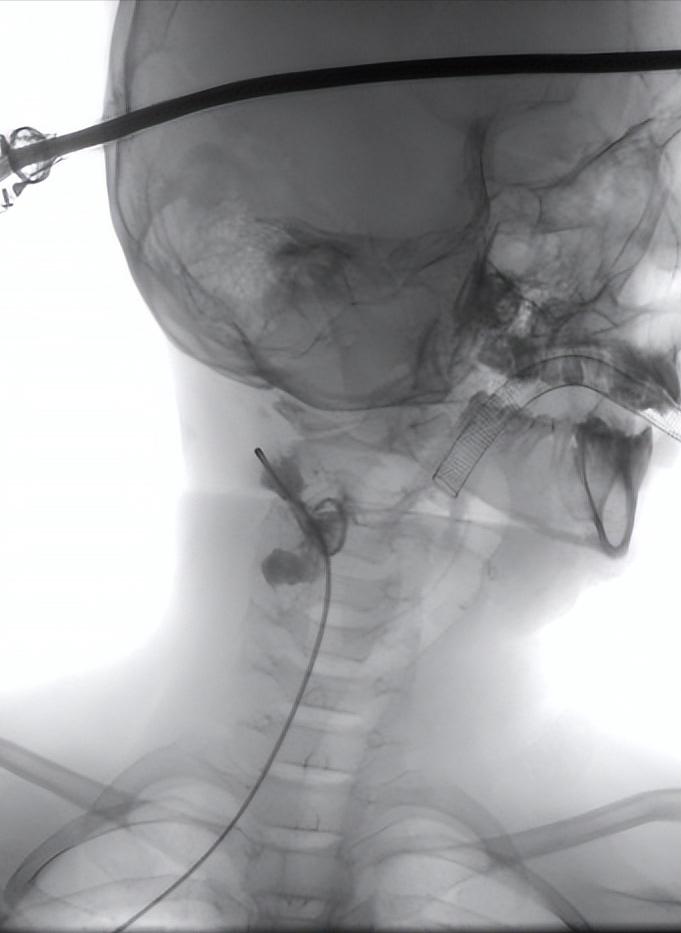

术中造影图片

经导管给予聚桂醇灌洗囊腔,后注入平阳霉素行硬化治疗。手术仅耗时半小时,手术过程非常顺利,术后孩子也没有任何不适。术后留置引流管,间断引流,配合硬化治疗。